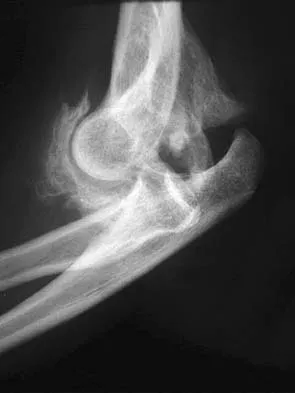

Anterior Cruciate Ligament (ACL) Rupture: Epidemiology, Anatomy & Surgical Management

ACL reconstruction is often indicated for symptomatic instability in active individuals, high-level athletes aiming to return to pivoting sports, and cases with concomitant knee injuries like meniscal tears. The goal is to restore knee stability, prevent further damage, and enable a safe return to desired physical activities after rehabilitation.